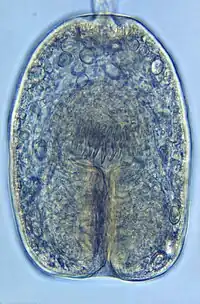

| Echinococcus granulosus protoscolex | |

Echinococcus granulosus, also called the hydatid worm, hyper tape-worm or dog tapeworm, is a cyclophyllid cestode that dwells in the small intestine of canids as an adult, but which has important intermediate hosts such as livestock and humans, where it causes cystic echinococcosis, also known as hydatid disease. The adult tapeworm ranges in length from 3 mm to 6 mm and has three proglottids ("segments") when intact—an immature proglottid, mature proglottid and a gravid proglottid.[1] The average number of eggs per gravid proglottid is 823. Like all cyclophyllideans, E. granulosus has four suckers on its scolex ("head"), and E. granulosus also has a rostellum with hooks. Several strains of E. granulosus have been identified, and all but two are noted to be infective in humans.[2]